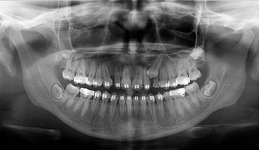

Pomocí tohoto přístroje je možné zjisti skutečnou situaci v čelistních kostech pacienta tedy množství kosti - můžeme změřit skutečnou šířku i výšku kosti, i kvalitu kosti (hustotu) v místě uvažované implantace. 3D (tříprostorové) zobrazení umožňuje

zvýšit prostorovou představu operatéra ještě před vlastní operací a zároveň pacientovi lépe objasnit a ukázat oblast plánovaného zavedení implantátu.

Pacient „neumí číst“ RTG snímky, ale díky 3D zobrazení vidí „svoji skutečnou čelist“ – např. jak je nízká či úzká, vidí průběh nervu nebo velikost čelistní dutiny, což mu umožní i pochopení nutnosti v některých případech provést pomocné zákroky

ještě před vlastním zavedením implantátu (více - Augmentace - kostní štěp, sinus lift, kostní granulát...).